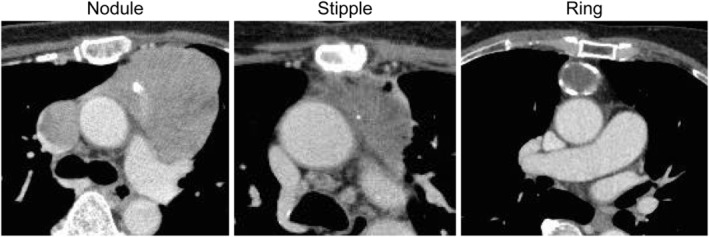

We collected data on clinical characteristics (such as calcification on CT findings, histology, Masaoka Stage, World Health Organization [WHO] stage) of patients with thymomas who were treated at our institution between 2000 and 2016 (Figure 1). The thymomas were classified as nodular (size around the node approximately >3 mm), stipple (size approximately <3 mm), and ring calcification (Figure 2). The study design was approved by the appropriate ethics review board of Tokushima University Hospital (approval number 3672). This study was a retrospective review of patient medical records from electronic medical records of Tokushima University Hospital. We published the information disclosure documents on the home page of the Tokushima University Hospital's website. The institutional review board (IRB) specifically waived the requirement for informed consent owing to the retrospective design of the study. We determined the procedures mentioned above on informed consent according to Japanese governmental guidelines. The IRB guidelines are equivalent to the guidelines of the Ministry of Education, Culture, Sports, Science and Technology and the Ministry of Health, Labor, and Welfare in Japan.

FIGURE 2.

Different calcification forms in thymomas. We classified calcification as nodular (we can trace around the node, size approximately >3 mm), stipple (size approximately <3 mm), and ring calcification

Among patients in the C group, various calcification patterns were observed (Table 2 and Figure 1). There were five cases each of stippled and nodular patterns, and one case of ring pattern. Cases with Masaoka stage III tended to have more stippled calcification patterns (3/5), whereas those with Masaoka stage IV tended to have more nodular calcification (3/5). There was no significant difference in the calcification forms (nodular and stipple) between invasive and noninvasive thymomas according to the Masaoka stage (p = 1.00). No significant differences in the calcification forms (nodular and stipple) were observed between patients with Masaoka stages III and IV (p = 0.4857). In addition, calcification forms (nodular and stipple) did not significantly differ between low‐ and high‐risk thymomas according to the histological classification (p = 0.4444). There was no significant difference in the calcification forms (nodular and stipple) for type B2 and B3 thymomas (p = 0.4643).